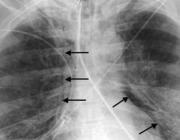

Регистрираха първи случай на Ку-треска за годината

23 Апр 2026 | 16:01 /КРОСС/ Регионалната здравна инспекция в Пловдив потвърди първи случай на ку‑треска за 2026 г. Засегнат е 67‑годишен мъж, който е приет в болница на 6 април с двойна бронхопневмония. След проведено лечение пациентът е изписан седмица ...